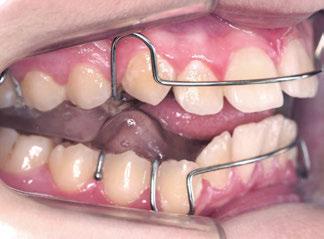

Transcurridos 7 meses, se sustituyó por un Twin Block para un segundo y definitivo avance (figuras 12 a 16).

Este último aparato funcional se mantuvo en boca durante 8 meses, tras haber conseguido la mejoría esperada en cuanto al aspecto facial (figura 17) y las relaciones oclusales (figuras 18 a 22). La mordida abierta lateral producida es fácilmente solucionable en la siguiente fase de tratamiento.